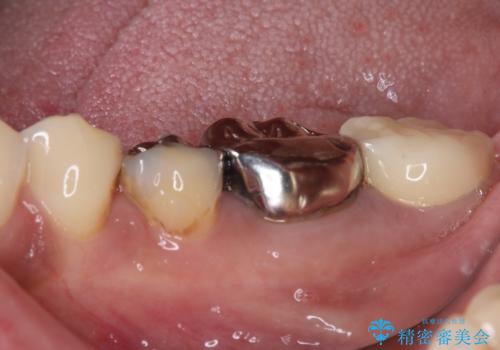

- 銀歯の奥が欠けてしまったとのことで来院された患者様です。

大きな銀歯が装着されており、その下からむし歯が広がっている状態でした。

特に症状はなく、神経組織も健全な状態であったため、むし歯を全て取り切った後にフルジルコニアクラウンにて補綴することとしました。

銀歯などを使用する保険診療は、歯との境界の適合が悪く、むし歯の再発リスクが高いため、長期的な観点から使用は推奨されません。